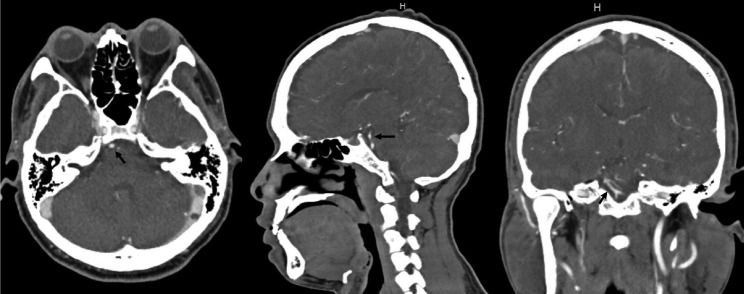

The Anterior Inferior Cerebellar Artery-Posterior Inferior Cerebellar Artery (AICA-PICA) common trunk is a rare variant of cerebral posterior circulation in which a single vessel originating from either the basilar or vertebral arteries supplies both cerebellum and brainstem territories. We present the first case of an unruptured right AICA-PICA aneurysm treated with flow diversion using a Shield-enhanced pipeline endovascular device (PED, VANTAGE Embolization Device with Shield Technology, Medtronic, Canada). We expand on this anatomic variant and review the relevant literature. A 39-year-old man presented to our treatment center with vertigo and right hypoacusis. The initial head CT/CTA was negative, but a 4-month follow-up MRI revealed a 9 mm fusiform dissecting aneurysm of the right AICA. The patient underwent a repeat head CTA and cerebral angiogram, which demonstrated the presence of an aneurysm on the proximal portion of an AICA-PICA anatomical variant. This was treated with an endovascular approach that included flow diversion via a PED equipped with Shield Technology. The patient's post-procedure period was uneventful, and he was discharged home after two days with an intact neurological status. The patient is still asymptomatic after a 7-month follow-up, with MR angiogram evidence of stable aneurysm obliteration and no ischemic lesions. Aneurysms of the AICA-PICA common trunk variants have a high morbidity risk due to the importance and extent of the territory vascularized by a single vessel. Endovascular treatment with flow diversion proved to be both safe and effective in obliterating unruptured cases.

小脑前下动脉-小脑后下动脉(AICA-PICA)共同干是大脑后循环的一种罕见变异,即由基底动脉或椎动脉的单一血管供应小脑和脑干区域。我们介绍了首例使用盾牌增强管道内血管装置(PED,加拿大美敦力公司的带盾牌技术的 VANTAGE 栓塞装置)进行血流分流治疗的未破裂右侧 AICA-PICA 动脉瘤病例。我们对这一解剖变异进行了详细阐述,并回顾了相关文献。一名 39 岁的男子因眩晕和右侧听力减退来到我们的治疗中心。最初的头部 CT/CTA 检查结果为阴性,但 4 个月后的磁共振成像检查发现右侧 AICA 有一个 9 毫米的纺锤形剥离动脉瘤。患者再次接受了头部CTA和脑血管造影检查,结果显示在AICA-PICA解剖变异的近端存在动脉瘤。患者接受了血管内治疗,包括通过装有盾牌技术的 PED 进行血流分流。患者术后恢复顺利,两天后出院回家,神经状况良好。经过 7 个月的随访,患者仍无症状,磁共振血管造影显示动脉瘤闭塞稳定,无缺血性病变。AICA-PICA 共干变异动脉瘤的发病风险很高,这是因为单根血管血管化区域的重要性和范围。事实证明,在未破裂的病例中,使用血流分流的血管内治疗既安全又有效。